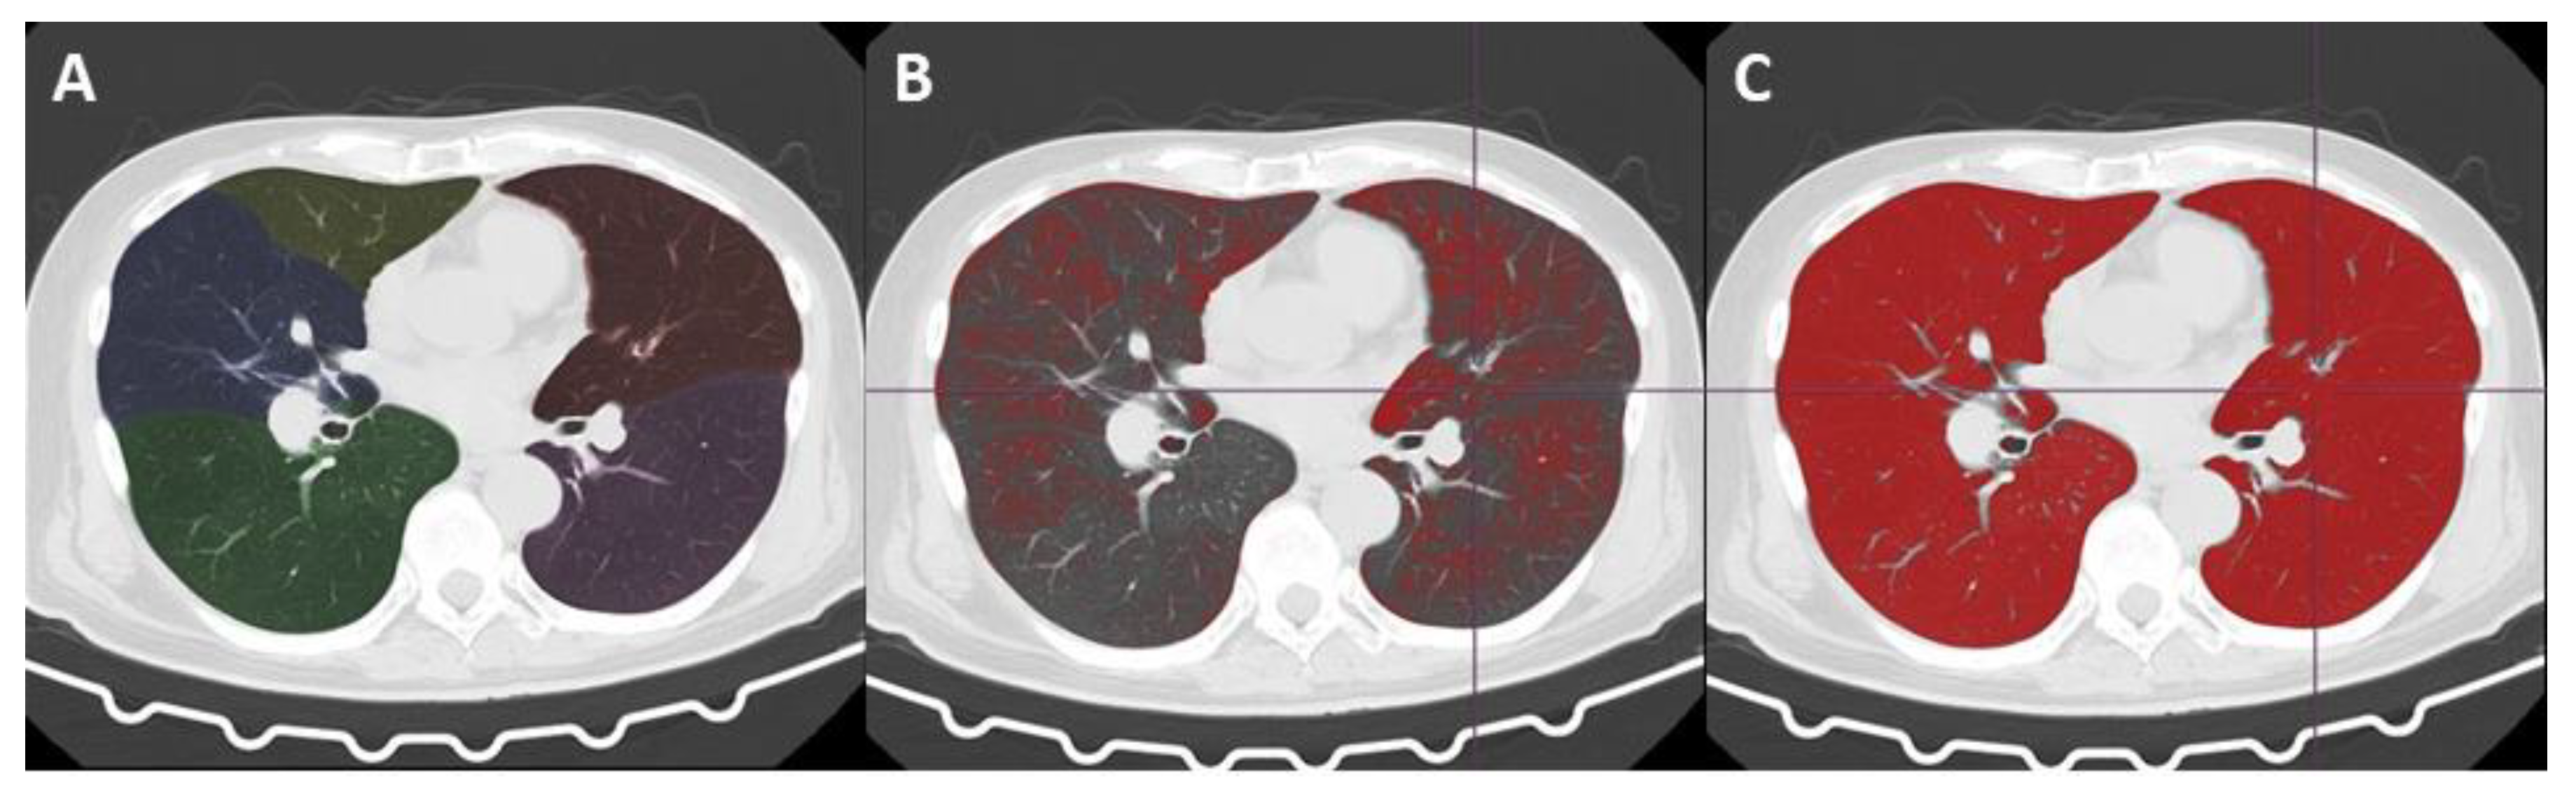

Automated Volume Analysis of the CT Images